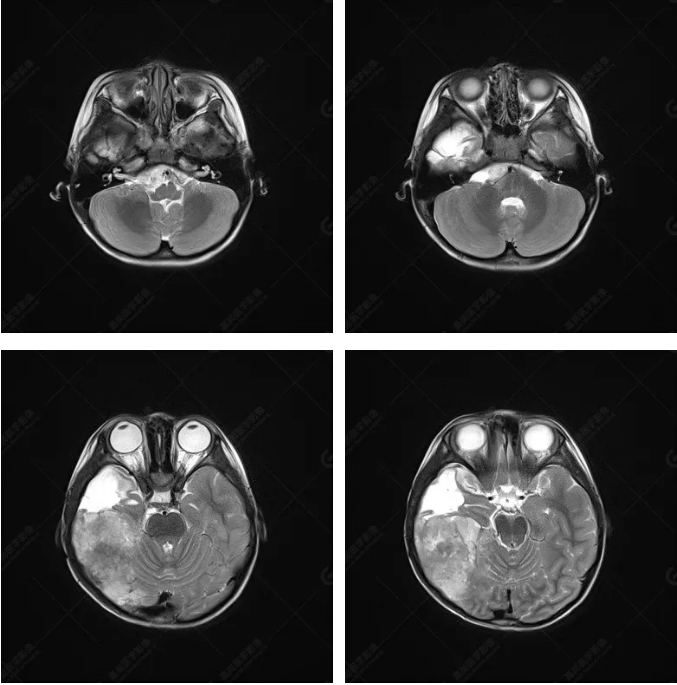

右側(cè)顳葉腫瘤切除術(shù)后(具體不詳):右側(cè)顳部骨質(zhì)不連續(xù)呈術(shù)后改變,右側(cè)顳葉術(shù)區(qū)見(jiàn)片狀長(zhǎng)T1長(zhǎng)T2信號(hào)影,F(xiàn)LAIR呈低信號(hào);術(shù)區(qū)后方右側(cè)顳枕葉見(jiàn)一巨大占位性病變影,邊界欠清,大小約6.2×5.8×4.3cm(前后×左右×上下),信號(hào)不均勻,T1WI呈等稍低信號(hào)間雜少許高信號(hào),T2WI呈高稍低混雜信號(hào),DWI示部分病灶彌散受限,相應(yīng)ADC圖減低,磁敏感序列見(jiàn)部分呈極低信號(hào),增強(qiáng)掃描可見(jiàn)明顯不均勻強(qiáng)化,鄰近硬腦膜及小腦幕增厚并明顯強(qiáng)化;另延髓右前方及右側(cè)橋小腦角區(qū)見(jiàn)一不規(guī)則形異常信號(hào)影,大小約3.2×1.3×3.7cm(左右×前后×上下),呈長(zhǎng)T1稍長(zhǎng)T2信號(hào),F(xiàn)LAIR呈等信號(hào),DWI未見(jiàn)受限,增強(qiáng)后明顯均勻強(qiáng)化,鄰近腦膜明顯強(qiáng)化。鄰近腦實(shí)質(zhì)及右側(cè)顳角明顯受壓;左側(cè)大腦半球未見(jiàn)局灶性信號(hào)異常,中線結(jié)構(gòu)稍左移。

右側(cè)顳葉腫瘤切除術(shù)后:現(xiàn)術(shù)區(qū)后方右側(cè)顳枕葉及延髓右前方占位,右側(cè)顳枕部硬腦膜及小腦幕明顯強(qiáng)化,結(jié)合既往影像資料,考慮為胚胎源性惡性腫瘤,如非典型畸胎樣/橫紋肌樣瘤(AT/RT)或原始神經(jīng)外胚層腫瘤(PNET)。

術(shù)后隨訪病理結(jié)果:非典型畸胎樣/橫紋肌樣瘤。